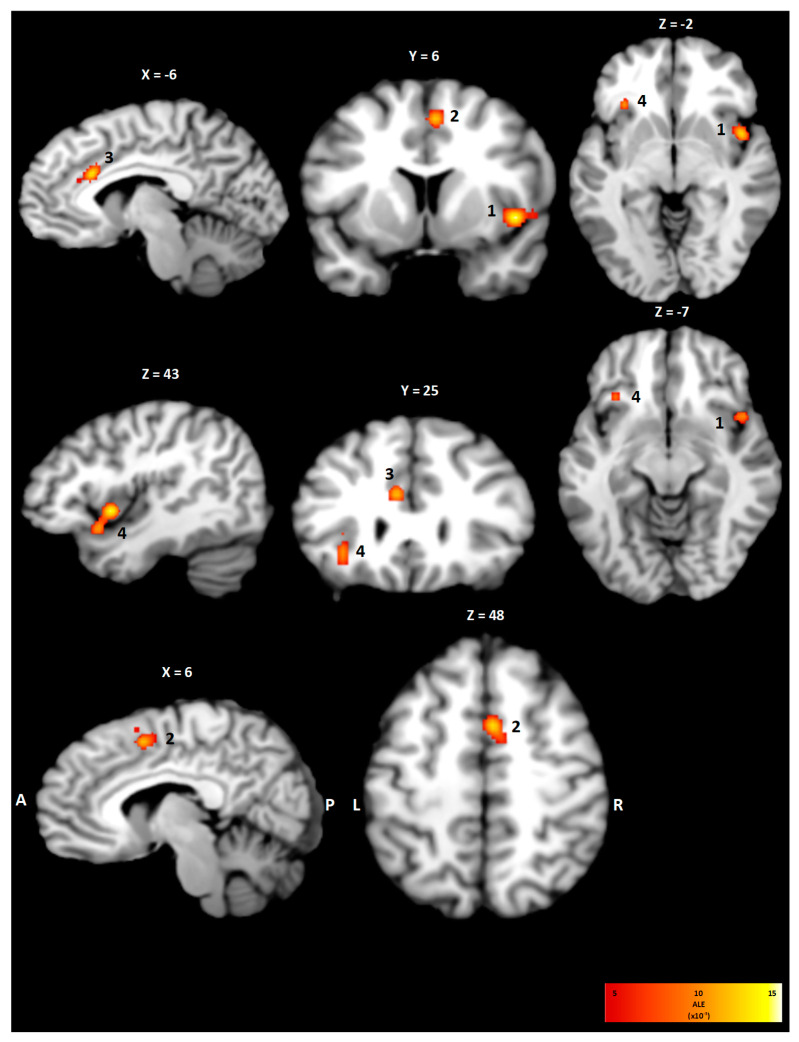

The sensation of dyspnea is related to various cardiopulmonary and neuromuscular diseases and is characterized by its sensory and affective qualities. Although there is a vast number of studies investigating its pathophysiology, less is known about the neuroanatomy of dyspnea perception. An activation likelihood estimation (ALE) meta-analysis of 13 studies investigating different breathing challenges using either PET or fMRI was performed to demonstrate the neuroanatomical correlates of dyspnea perception. The ALE meta-analysis was performed using the GingerAle software 3.0.2 and was displayed with the Mango software 4.1. Synthesizing the results of all included studies, clusters involving the insula and cingulated cortex in both hemispheres were observed. Subgroup analysis for the restrained breathing condition revealed activation involving the right and left cingulate cortex and left anterior cingulate cortex. For the loaded breathing condition, statistically significant activation was found for the postcentral gyrus, the superior temporal gyrus, and the right thalamus. The combined ALE map for both conditions showed activity patterns in the right cingulate cortex, the right insula, and the right thalamus. This ALE meta-analysis demonstrates that two separate neuronal pathways related to either the affective or intensity domain are involved in the central processing of dyspnea perception.